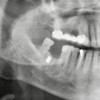

Merkeze bağlı Aslahlı Mahallesi''nde evli ve 2 çocuk babası emekli memur Faik Akın, Binali Yıldırım Üniversitesi Ağız ve Diş Sağlığı Eğitim ve Araştırma Hastanesi Ağız Diş ve Çene Cerrahisi Bölümü''ne diş tedavisine gitti. Akın''ı muayene ettikten sonra çekilen röntgen filmini inceleyen Dr. Öğretim Üyesi Yakup Gülnahar, yanağında bir parça olduğunu belirledi. Muayenede 15 yıl önce yaşadığı bir olayı hatırlayan Akın, benzinli hızar ile odun kestiği sırada zincirin koptuğunu ve daha sonra yanağında şişlik oluştuğunu söyledi. Dr. Gülnahar''ın mıknatıs ile yaptığı kontrolde parçanın metal olduğu tespit edildi. Dr. Gülnahar, ameliyat ile Akın''ın yanağındaki metal zincir parçasını aldı.

Dr. Öğretim Üyesi Yakup Gülnahar da "Faik bey, rutin diş tedavisi için bize geldi. İstenilen röntgen filminde bir cisme denk geldik. Kendisine ''İmplant yaptırdınız mı?'' diye sordum. ''Hayır'' dedi. Bu sefer, hasta geçmişinde yaşadığı bir kazadan bahsetti. Kontrol ettiğimiz de mıknatısın şişliği çektiğini gördük. Başarılı bir operasyon ile demir parçasını aldık. Hasta şu anda gayet iyi" diye konuştu.